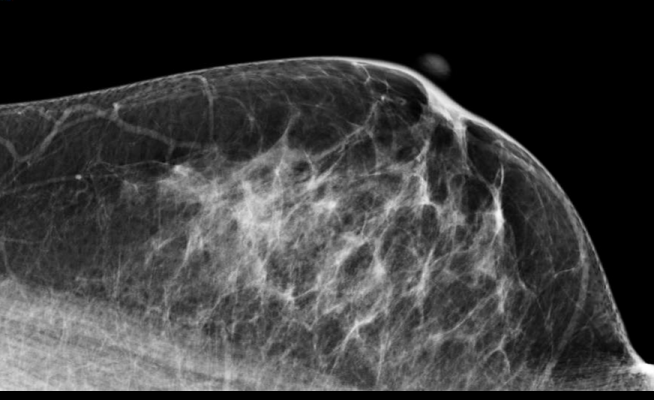

With an estimated 60 million women in the United States undergoing regular breast cancer screenings, Mammography Quality Standards Act (MQSA)-certified imaging centers perform nearly 40 million mammography procedures each year. It is not uncommon for women to move between medical facilities, or to new cities or states, during their recommended mammographic age. The Mammosphere network saves providers time, energy and resources by allowing them to securely access an individual patient's prior exams, regardless of timing or location of the performed study.

Breast imaging centers utilizing the Mammosphere network have demonstrated significant improvements to the efficiency and effectiveness of their breast cancer screening programs. After the introduction of Mammosphere at one facility in 2015, there was a 48 percent reduction in mammograms read without prior comparison, and a 73 percent decrease in patient callbacks due to false-positive findings. These improvements in the quality of care prevented the cost of unnecessary imaging and testing, kept new screening exams on schedule for the center, and, most importantly, saved patients weeks of emotional turbulence and unwarranted concern about their outcome.